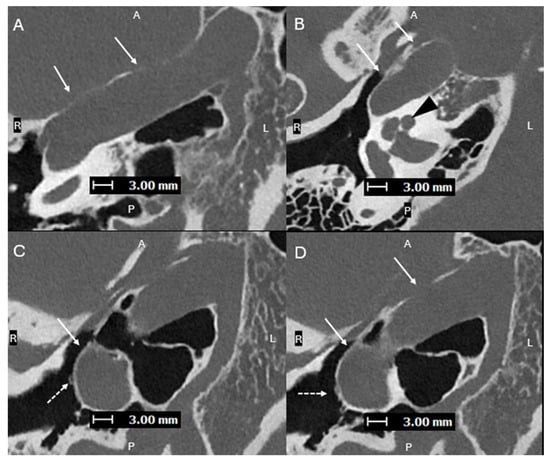

Figure 3. Axial oblique images (superior to inferior (AD), with A, P, L, R for orientation donating anterior, posterior, left, and right respectively) from a PCD-CT temporal bone study—with same acquisition and reconstruction parameters as Figure 1—demonstrating a lateralized R ICA (solid arrows). (B) shows the ICA lateral to the midportion of the basal turn of the cochlea (black arrowhead). (C,D) show the normal R ITC visualized laterally (dashed arrows), proving that this is a lateralized ICA and not an aberrant ICA. A lateralized ICA is defined as the genu of the vertical and horizontal segments of the petrous ICA positioned lateral to the midportion of the basal turn of the cochlea in the axial plane. Importantly, the ITC is not affected, which helps to distinguish a lateralized ICA from an aberrant ICA [8]. Skull base foramina, such as the inferior tympanic canaliculus, are much better seen on PCD-CT, which can greatly help when trying to differentiate between an aberrant ICA and a lateralized ICA, as shown in cases 2 and 3 [9]. On EID-CT, it can be difficult to differentiate between a lateralized ICA and an aberrant ICA.